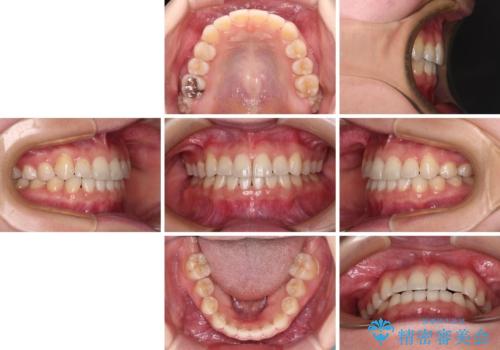

順調に後方移動することができ、わずか1年強で治療を終えることができました。

顎骨が小さいので第二大臼歯が欠損しても負担は少ないと思いますが、奥歯でもっとしっかりと咬みたいということであれば、インプラント補綴治療を4本分行うこととなります。